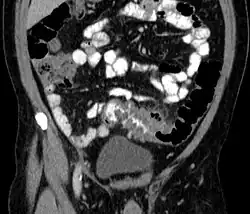

People with the above symptoms are commonly studied with computed tomography, or a CT scan.[37] Ultrasound can provide preliminary investigation for diverticulitis. Amongst the findings that can be seen on ultrasound is a non-compressing outpouching of bowel wall, hypoechoic and thickened wall, or an obstructive fecalith at the bowel wall. Besides, bowel wall oedema with adjacent hyperechoic mesentery can also be seen on ultrasound. However, a CT scan is the mainstay of diagnosing diverticulitis and its complications.[12] The diagnosis of acute diverticulitis is made confidently when the involved segment contains diverticula.[38] CT images reveal localized colon wall thickening, with inflammation extending into the fat surrounding the colon.[39] Amongst the complications that can be seen on CT scan are: abscesses, perforation, pylephlebitis, intestinal obstruction, bleeding, and fistula.[12]